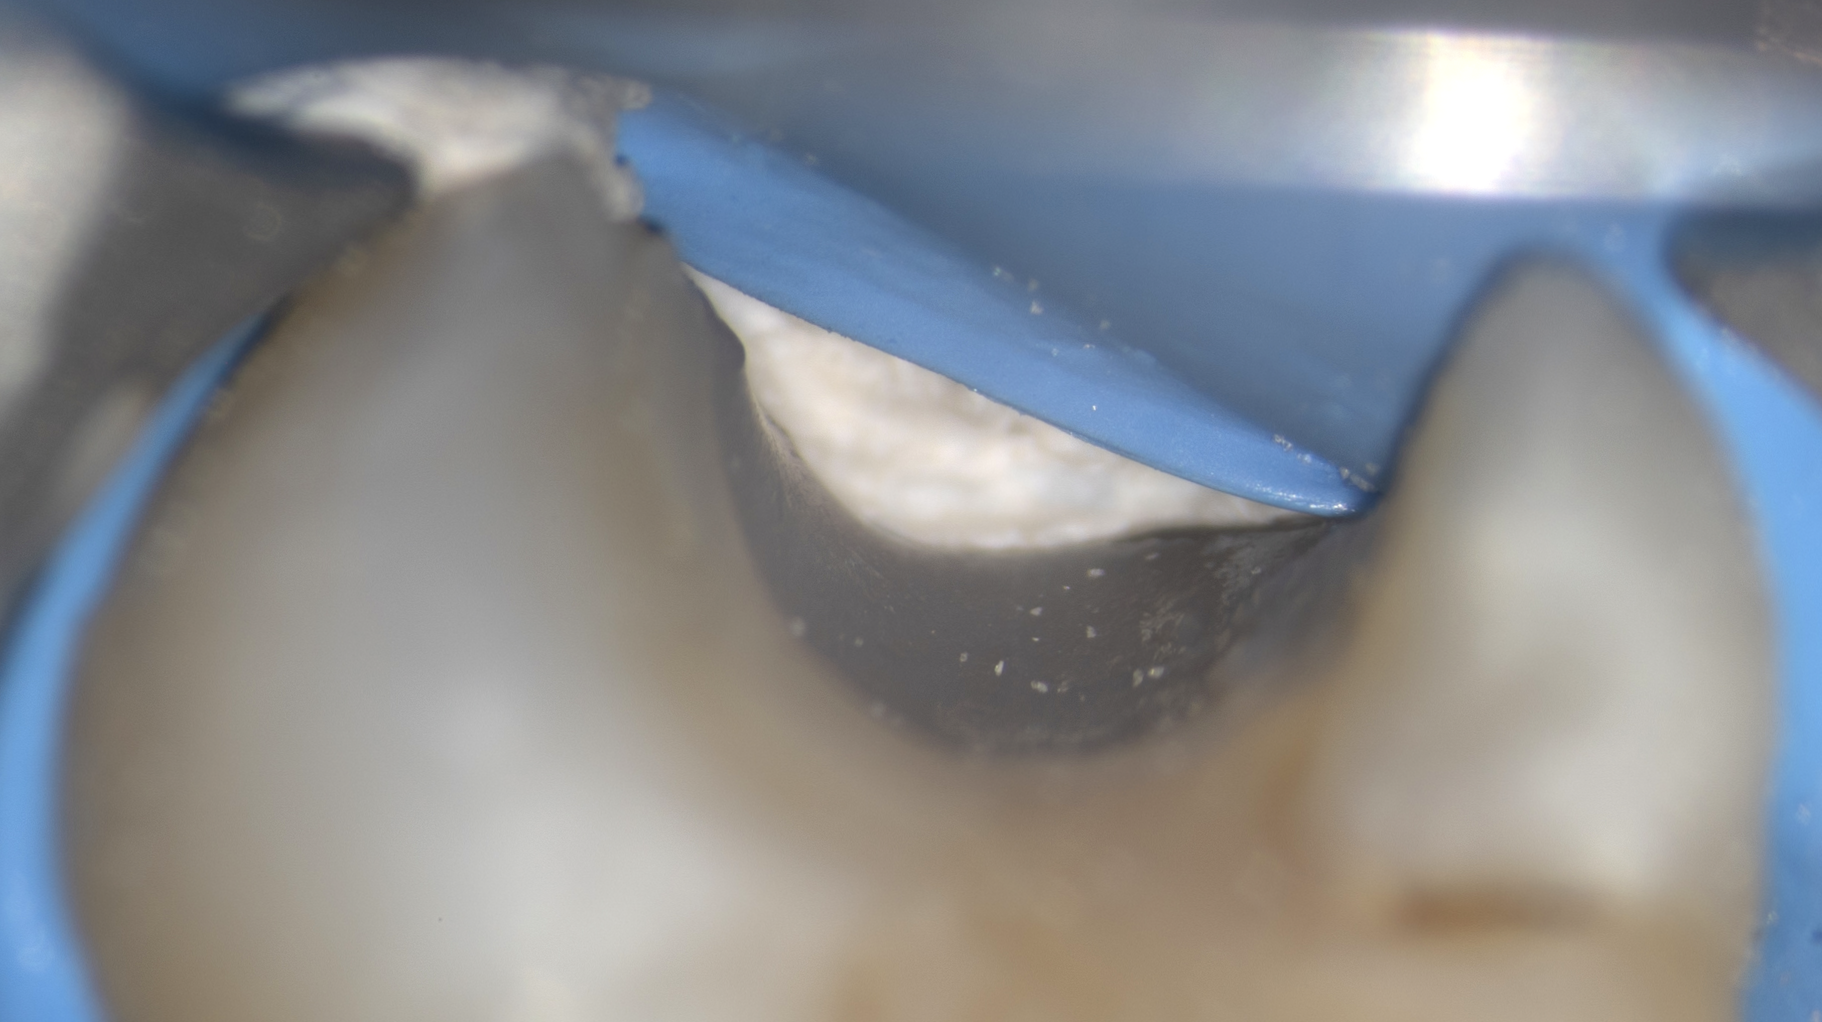

Clinical case

Direct pulp capping: 90.4% success rate